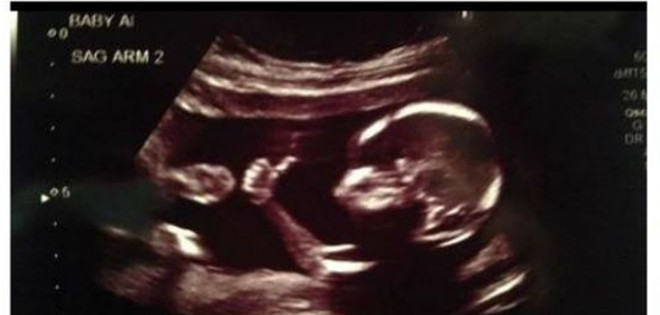

En el eco, el feto de 18 semanas aparece levantando el pulgar y mostrando el típico gesto de OK.

En ella, el feto de 18 semanas aparece levantando el pulgar y mostrando el típico gesto de 'OK, todo va bien'.

Esa no fue la única sorpresa de la ecografía para los padres. También lo fue conocer la noticia de que en realidad el pequeño de la imagen no vendría sólo sino que lo haría acompañado: iban a tener gemelos.